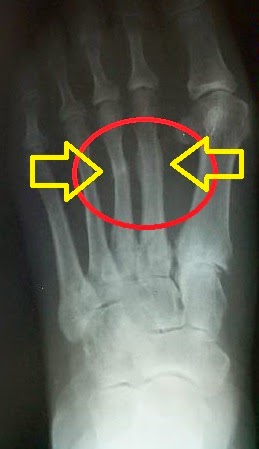

Stress fractures can occur to any bone in our bodies, but our feet are the most common location. In case you have additional questions or doubts, you can forward them to me, and i shall be glad to help you out. Poor technique or training errors can also contribute to the likelihood of sustaining a stress fracture of the foot. Stress fractures of the foot and ankle. How can you tell the difference between the two? How can you tell the difference? Tendonitis & stress fractures are common foot and running injuries. Metatarsal stress fractures the most common site for stress fractures of the foot is the metatarsal bones, but the most common site in the body for a stress fracture is the tibia. Stress fracture on top of the foot. Keep reading to learn more about the differences between plantar fasciitis and tendonitis. I don't know if i can tell the difference between stress fracture pain and tendinitis pain. This type of fracture can happen to any of the foot when they are fatigued or overloaded, they cannot absorb the shock and stress of repeated impacts, and end up transferring the stress to nearby bones. How to identify a stress fracture. Where do stress fractures happen? Stress fractures on the feet bones. Most stress fractures are caused by overuse and repetitive activity, and are common in runners and athletes who participate in running sports, such as soccer and basketball. A little pain in my foot but most of the pain is higher up, pointing more to a strain than tendonitis.